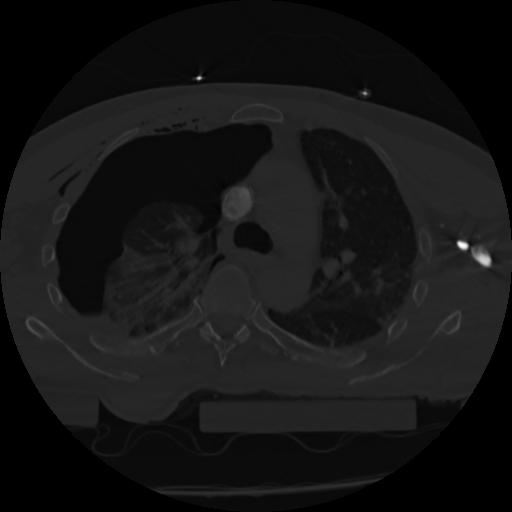

22 ANGIO,CE,Vol,0.5,ANGIO,,